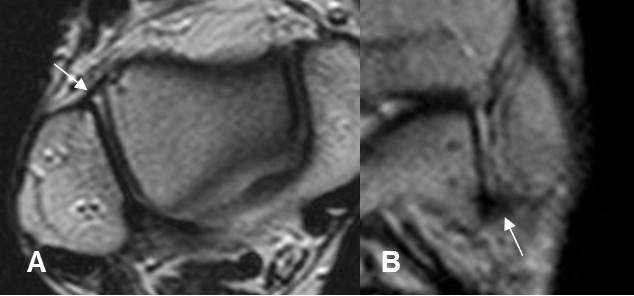

Las contusiones de la microtrabécula aparecen por fuerzas de impactación y compresión (3). Su ubicación permite conocer el mecanismo del trauma y la dirección de la energía, para buscar lesiones asociadas de músculos y ligamentos. Se aprecian como áreas mal definidas hipointensas en T1, hiperintensas en T2 y STIR. (1). (Fig 27, 28 y 29).

Fig 27. Contusión osea.

A: Rx AP. No se aprecian signos de lesión traumática.

B: RM coronal y C: RM sagital en STIR. Contusión osea en la parte postero-superior del platillo tibial medial.

Fig 28. Mecanismo del trauma directo.

A: RM coronal en STIR. Contusión osea en el compartimiento medial, que puede lesionar las estructuras de la esquina posterolateral y el LCL.

B: RM coronal en STIR. Contusión del cóndilo femoral lateral, debiendo descartar lesión del LCM.

C: RM coronal en STIR. Contusión en la parte posterior de la tibia, por lo que se debe buscar lesión del LCA

D: Contusión en la parte anterior de la tibia y cóndilo femoral medial, a descartar lesión del LCP y esquina posterolateral.

Fig 29. Contusión ósea.

RM sagital en STIR. Clásica contusión del platillo tibial y cóndilo femoral lateral, con signo de la muesca, encontrado en rupturas del LCA.